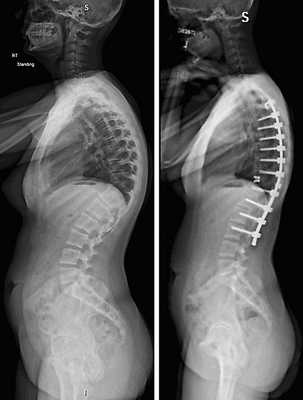

Стабилизация поясничного отдела.

Коррекция кифоза грудного отдела.